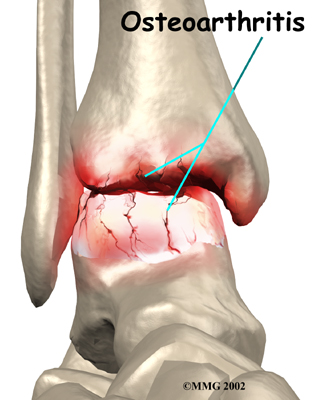

OA is usually considered a type of degenerative arthritis, or wear-and-tear arthritis. Doctors consider OA pretty much the same whether it appears years after an injury to the joint or whether it appears without any history of injury. It behaves more or less the same way.

Injury to a joint, such as a bad sprain or fracture, can cause damage to the articular cartilage. The cartilage can be bruised when too much pressure is exerted on it. This damages the cartilage, although if you look at the surface it may not appear to be any different. The injury to the material doesn't show up until months later. Sometimes the cartilage surface is damaged even more severely, and pieces of the cartilage are ripped from the bone. These pieces do not heal back and usually must be removed from the joint surgically. If not, they may float around in the joint, causing the joint to catch and be painful. These fragments of cartilage may also do more damage to the joint surface.

Once this cartilage is ripped away, it does not normally grow back. Unlike bone, holes in the surface are not simply replaced by the cartilage tissue around the hole. Instead the defects are filled with scar tissue. The scar tissue that forms is not nearly as good a material for covering joint surfaces as the cartilage it replaces. It just can't support weight and isn't smooth like true articular cartilage.

Over many years this imbalance in the joint mechanics can lead to damage to the articular surface. Since articular cartilage cannot heal itself very well, the damage adds up. Finally, the joint is no longer able to compensate for the increasing damage, and it begins to hurt. The damage occurs well before the pain begins.

Pain is the main problem with arthritis of any joint. This pain occurs at first only related to activity. Usually, once the activity gets underway there is not much pain, but after resting for several minutes the pain and stiffness increase. Later, when the condition worsens, pain may be present even at rest. The pain may interfere with sleep. The joint may swell, fill with fluid, and feel tight, especially following increased activity. As the articular cartilage starts to wear off the joint surface, the joint may squeak when moved. Doctors refer to this sound as crepitation.

When OA has reached a very severe stage, the bone itself under the articular cartilage may become worn away. This can lead to increasing deformities around the joint. In the final stages, the alignment of the bones can begin to form odd angles where they meet at the joint.